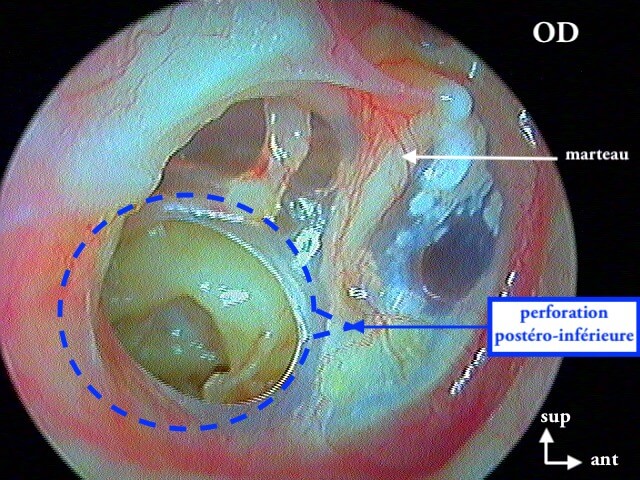

Une otite séromuqueuse droite perforée (et non otite moyenne aiguë)

9 OTITE MOYENNE CHRONIQUE (OMC) NON CHOLESTÉATOMATEUSE

Perforation , otorrhée à répétition, otite muqueuse dans la caisse, lyse ossiculaire, rétraction tympanique. La limite entre l'otite atéléctasique perforée et l'otite moyenne chronique non cholestéatomateuse est souvent ésotérique...